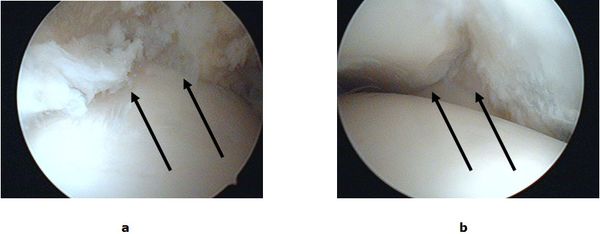

Bei Schmerzen auf Grund von Narbenbildungen und Einklemmungen von Gelenkkapsel und Schleimhaut (meniskoides Syndrom, Impingement) ist die Gelenkspiegelung die Therapie der Wahl. Ein minimalinvasives Verfahren bei dem durch zwei kleine Schnitte (kleiner 1cm) nahezu das ganze Gelenk eingesehen werden kann. Während der Spiegelung wird mit speziell geformten Feininstrumenten das krankhaft veränderte Gewebe entfernt und die Einklemmung beseitigt.

Abb.2: a Eingeklemmtes Narbengewebe im Gelenkspalt. b Freie Einsicht in den Gelenkspalt nach Entfernung des Narbengewebes.